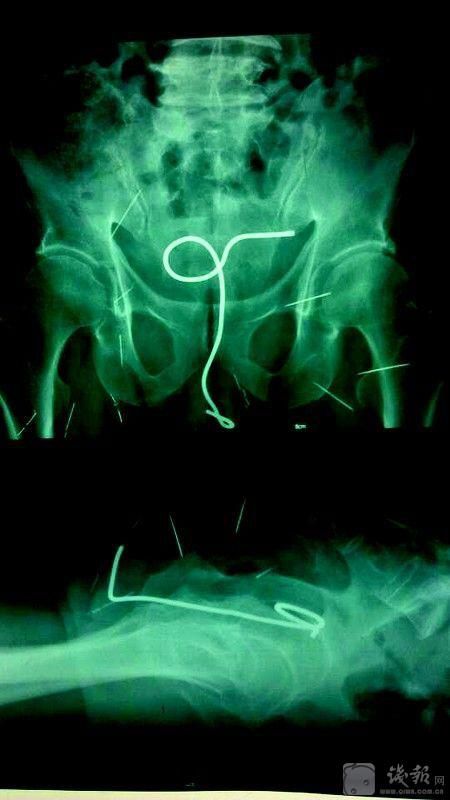

杭州市三医院泌尿外科主任诸靖宇说,不久前,他才接诊过一例尿道异物的患者,对方是一位40来岁的男性,因尿频、尿急、合并血尿有半个月时间而上医院就诊,经膀胱超声检查,发现膀胱中有一团异物,最后用膀胱镜取出,才弄明白是一团铜丝,展开来足足有6—7CM长。

起初,该男子还想隐瞒自己往尿道塞异物的事实,直到医生们帮他取出异物之后,他才轻描淡写地说了几句,因为数月前感到尿道奇痒无比,盐水洗、双手揉……试了好多方法都没能止痒,最后也不知道怎么回事,他就想到了把一根铜丝塞进尿道,绝了,还真不痒了,而且很舒服。只是,因感觉太好,铜丝越塞越深,最后一不小心全进去了。

<p>诸主任说,这位患者描述的是大部分尿道异物患者的普遍经历。面对这类情况,他们一般会按异物的大小分两类来处理,异物小一点的用膀胱镜直接取,而异物大一点的则得打开膀胱来取异物。